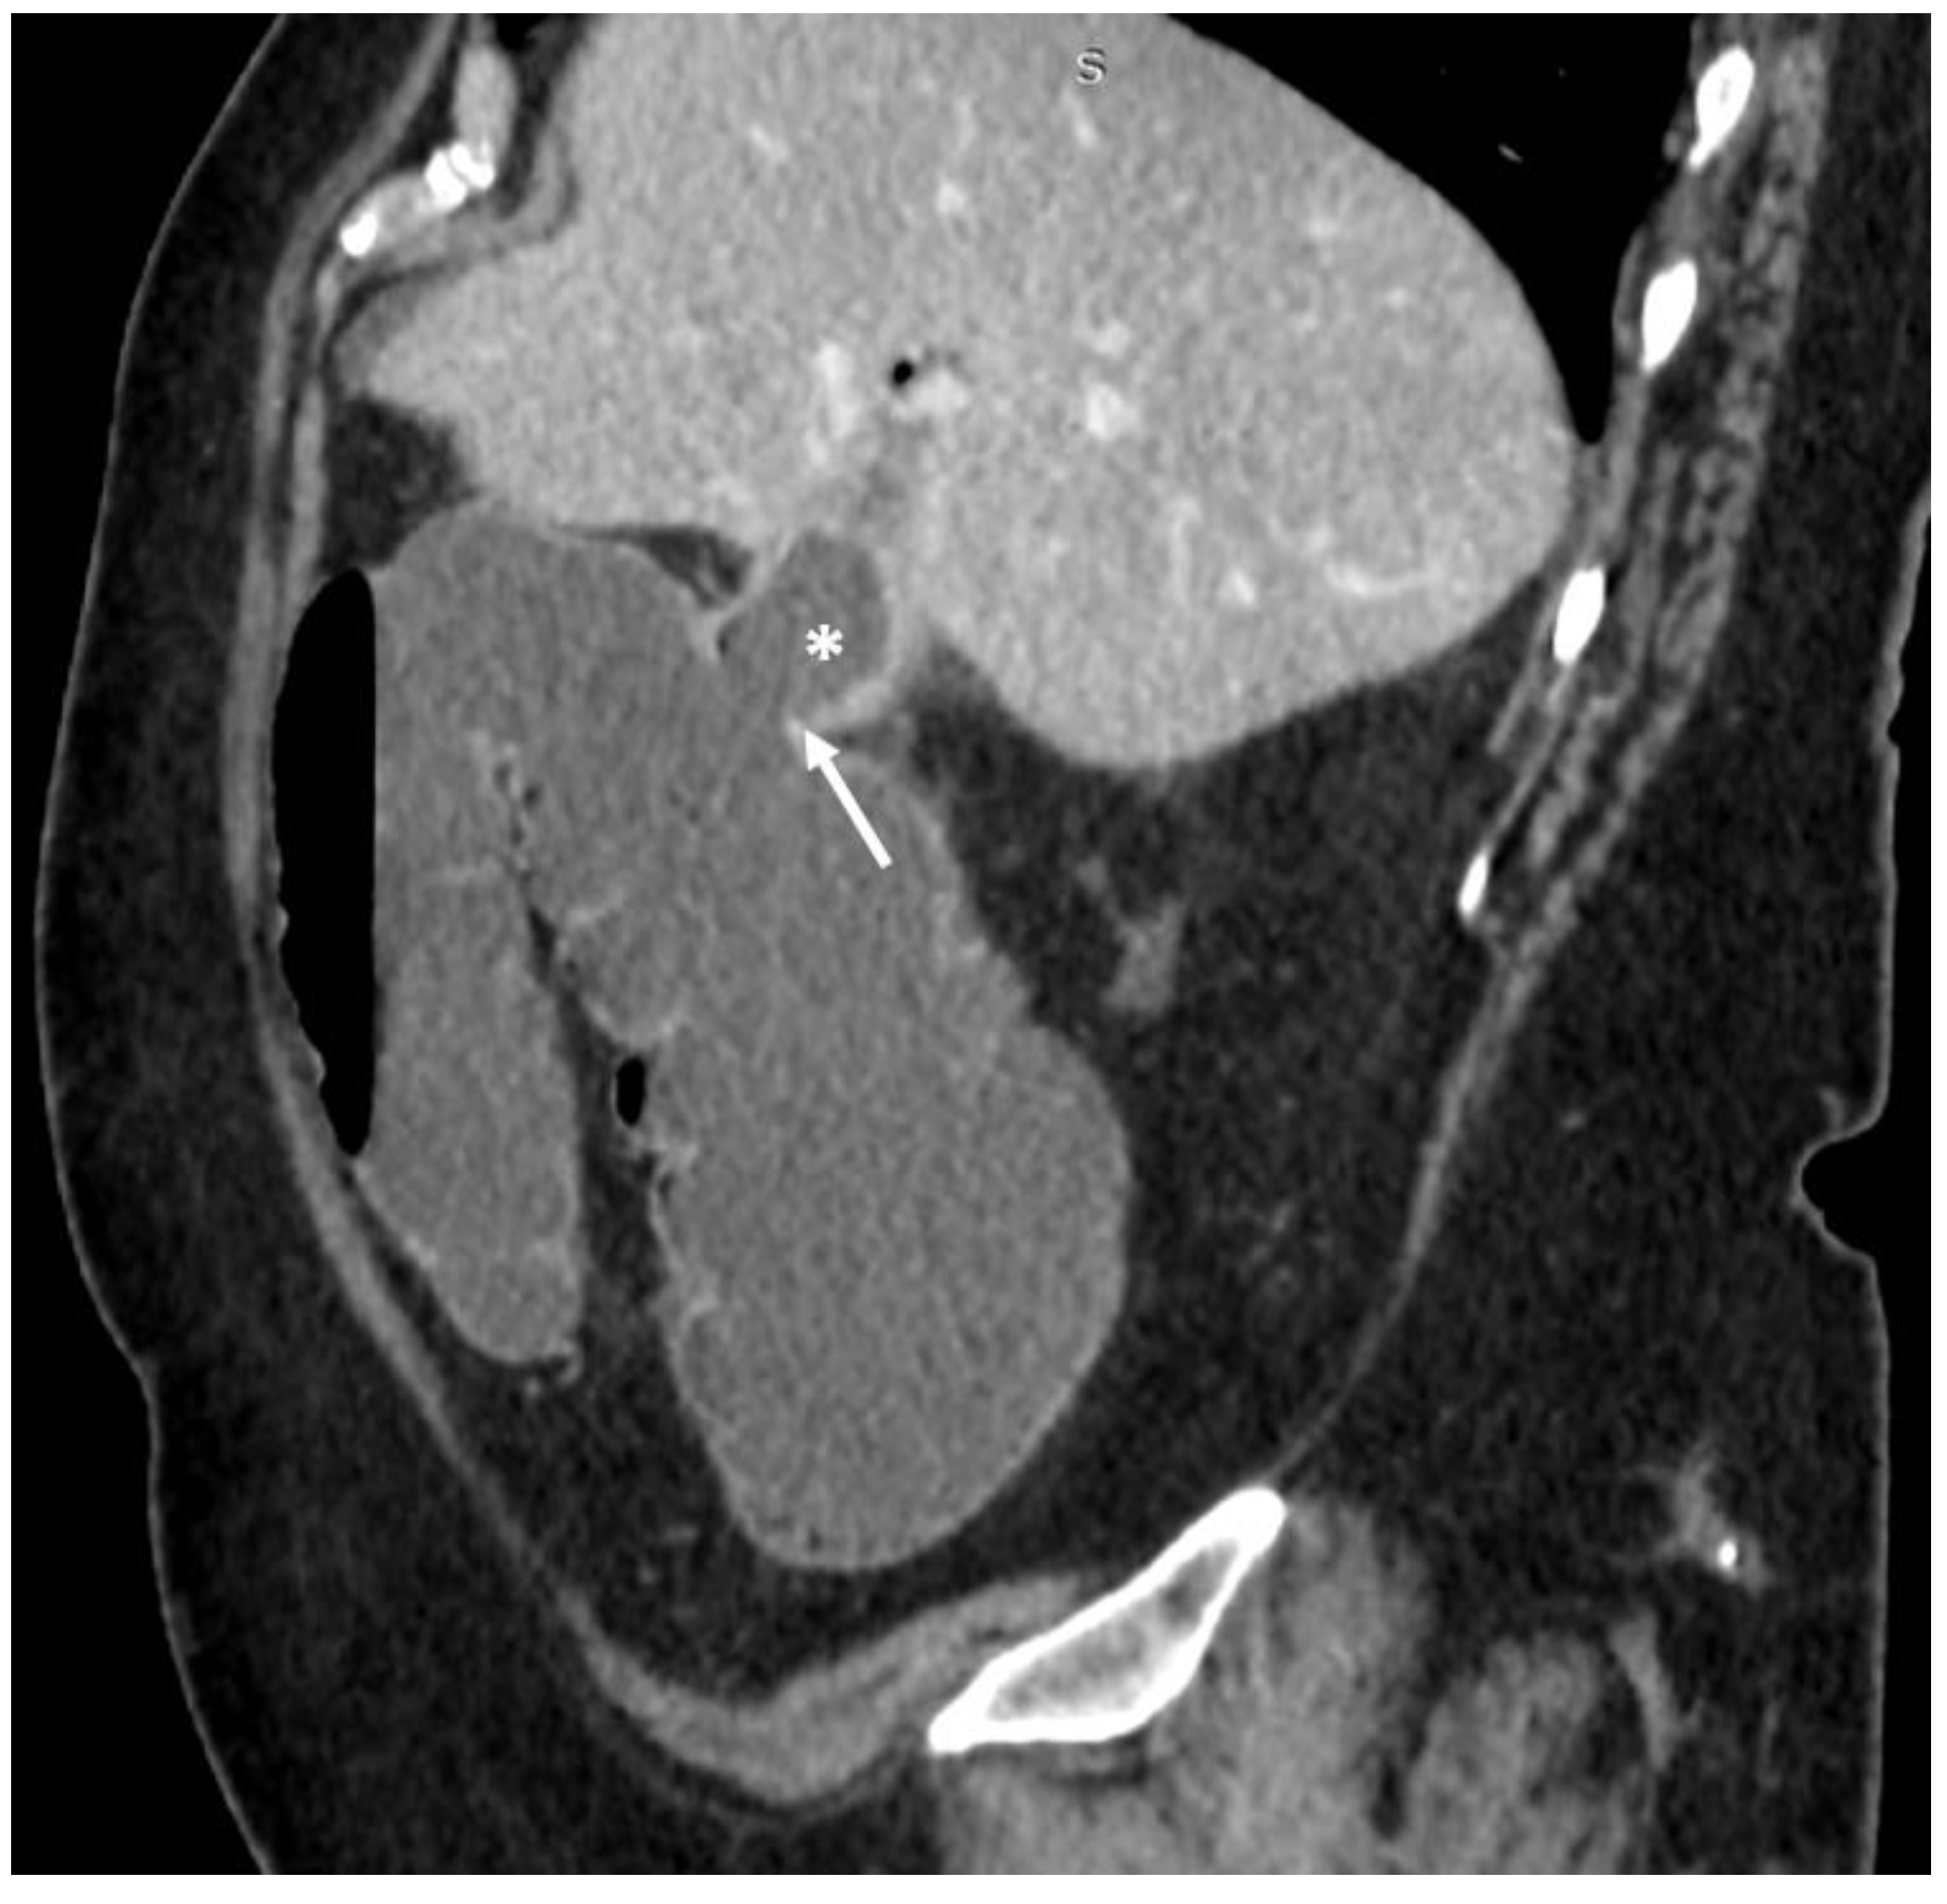

| F, 82 | 25 | III | Laparoscopically assisted enterolithotomy | 95 | Ileum | 3 × 3 cm | 3 | 14 | Good: recovery |

| F, 48 | 40 | III | Laparoscopically assisted enterolithotomy | 70 | Ileum | 3 × 4 cm | - | 10 | Good: recovery |

| F, 85 | 47 | IV | Laparoscopically assisted enterolithotomy | 60 | Ileum | 4 × 3 cm | 12 | 13 | Good: recovery |

| F, 69 | 12 | III | Colonoscopy | 115 | Sigmoid colon | 5 × 4 cm | - | 10 | Good: recovery |

| F, 87 | 2 | IV | Laparotomy with enterolithotomy | 35 | Jejunum | 4 × 3 cm | 5 | 7 | Poor: death |